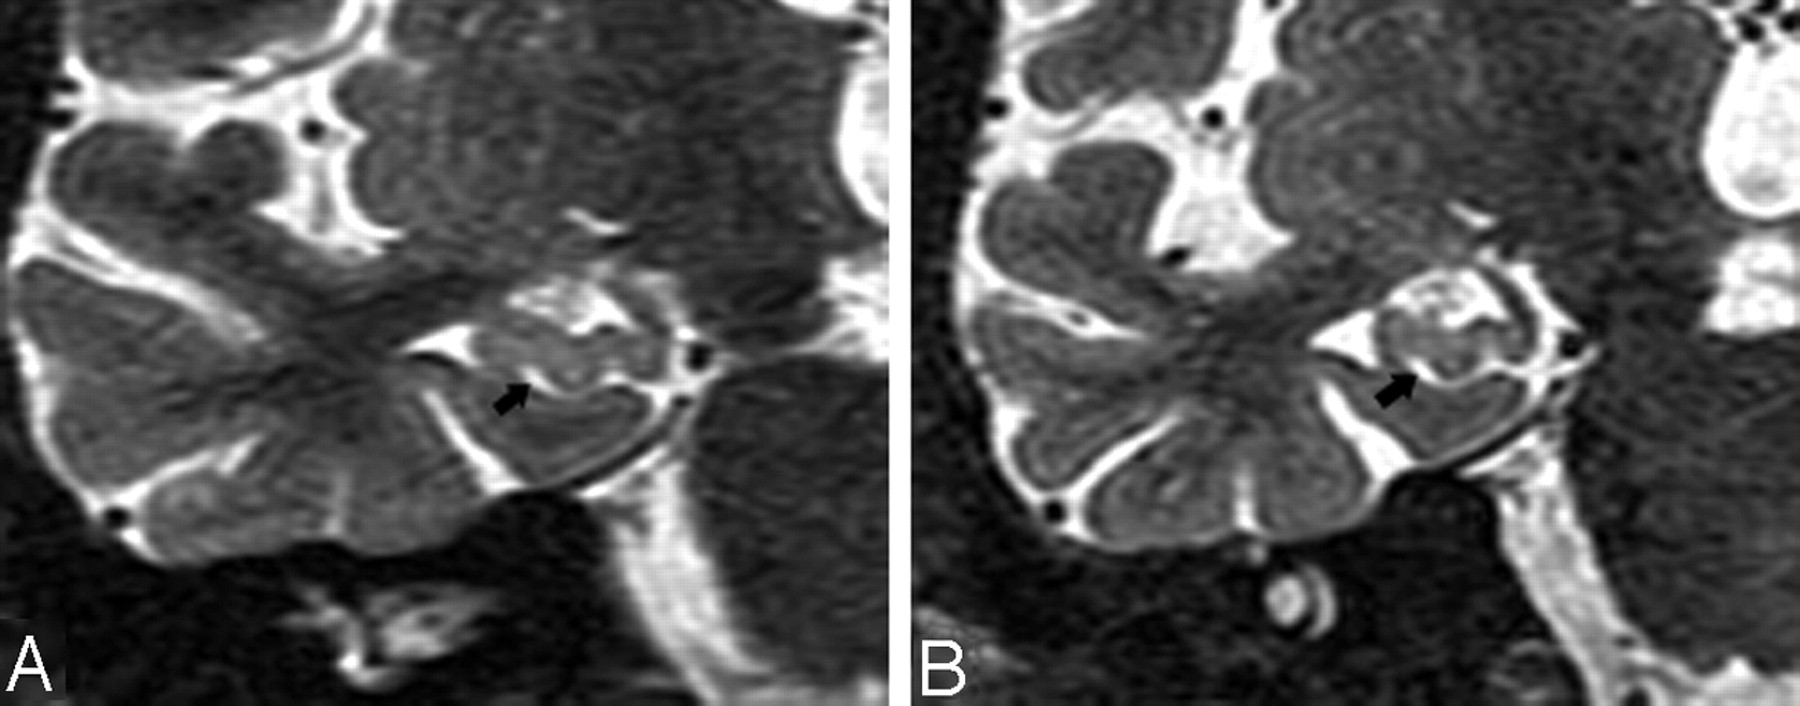

In the coronal plane, the differentiation of a HSC in the presence of a dilated uncal sulcus is challenging. As seen in Figs 4A and 5A, these CSF structures look very similar. They can be differentiated by identifying the medial to lateral course of the uncal sulcus through its continuation with the ambient cistern. This relationship is clearly seen in a 3-year follow-up, when the uncal sulcus, but not the HSC, changed over time (Figs 4B and 5B). In the axial plane, the differentiation of a HSC from the PHF and from uncal sulcus can be difficult (Figs 6A and 7A). Comparing them, the HSC is again the more lateral and distributed along the vestigial primary hippocampal sulcus. We conclude that the coronal plane (Figs 6B and 7B) is most helpful for distinguishing between them.

T2 short-τ inversion recovery (STIR) MR coronal image obtained from a 74-year-old male normal control (NC) patient. A, Arrowhead shows a small hippocampal sulcus residual cavity (HSC); arrow shows perihippocampal fissures (PHF) (uncal sulcus). B, 3-year follow-up scan. Comparing A and B, there is progressive dilation of the uncal sulcus (arrow), but no obvious change in the size of the HSC (arrowhead).

T2 short-τ inversion recovery (STIR) MR coronal image was obtained from a 73-year-old male normal control (NC) patient. Arrows show a dilated uncal sulcus and no hippocampal sulcus residual cavity (HSC). B, 3-year follow-up.